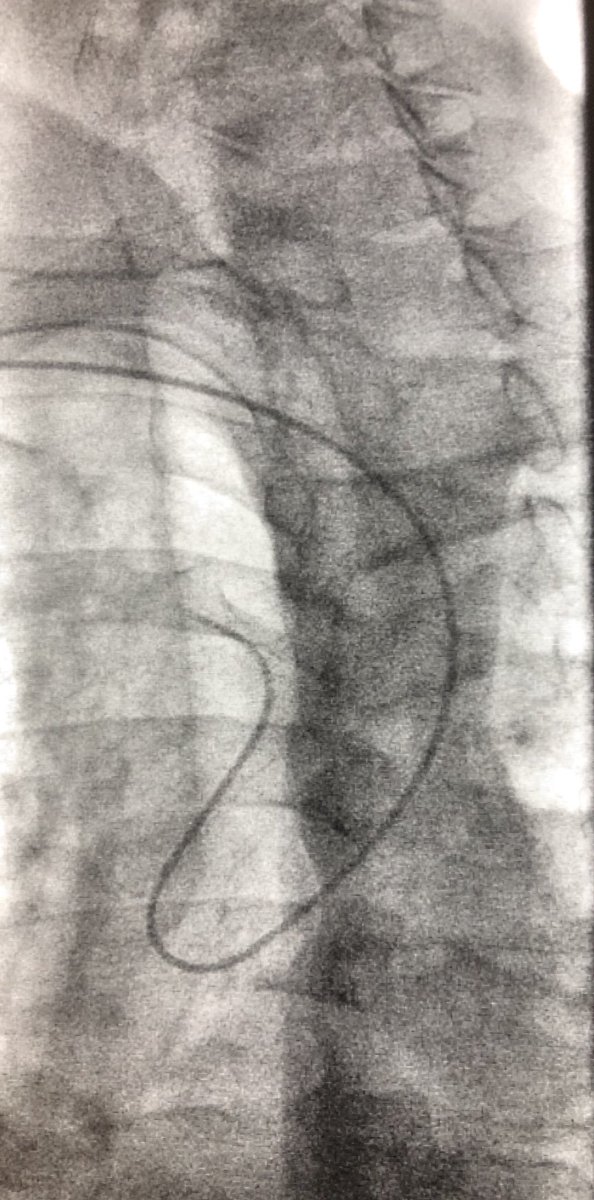

7.4 cm AAA w/ bilateral CIA aneurysms successfully treated with EVAR and bilateral iliac branch devices w/ coil embolization of the anterior branch of the R IIA. Even the daily disruption related to COVID can’t diminish the satisfaction of a case coming together #SCAIPAD #TCAVI